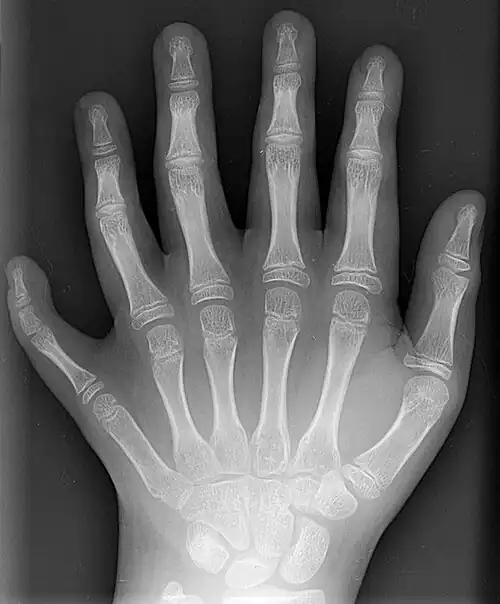

X-ray showing joints -

Hand bone anatomy

The skeleton of the human hand consists of 27 bones:[10] the eight short carpal bones of the wrist are organized into a proximal row (scaphoid, lunate, triquetral and pisiform) which articulates with the bones of the forearm, and a distal row (trapezium, trapezoid, capitate and hamate), which articulates with the bases of the five metacarpal bones of the hand. The heads of the metacarpals will each in turn articulate with the bases of the proximal phalanx of the fingers and thumb. These articulations with the fingers are the metacarpophalangeal joints known as the knuckles. At the palmar aspect of the first metacarpophalangeal joints are small, almost spherical bones called the sesamoid bones. The fourteen phalanges make up the fingers and thumb, and are numbered I-V (thumb to little finger) when the hand is viewed from an anatomical position (palm up). The four fingers each consist of three phalanx bones: proximal, middle, and distal. The thumb only consists of a proximal and distal phalanx.[11] Together with the phalanges of the fingers and thumb these metacarpal bones form five rays or poly-articulated chains.

There are numerous sesamoid bones in the hand, small ossified nodes embedded in tendons; the exact number varies between people:[7] whereas a pair of sesamoid bones are found at virtually all thumb metacarpophalangeal joints, sesamoid bones are also common at the interphalangeal joint of the thumb (72.9%) and at the metacarpophalangeal joints of the little finger (82.5%) and the index finger (48%). In rare cases, sesamoid bones have been found in all the metacarpophalangeal joints and all distal interphalangeal joints except that of the long finger.